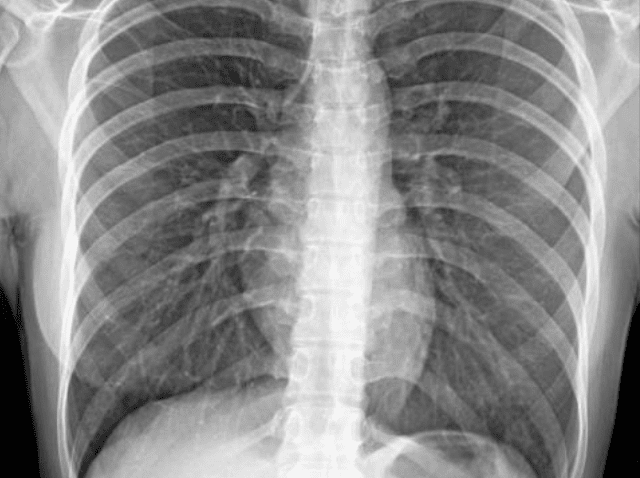

Normales Röntgenbild des Brustkorbs 2

Normales Röntgenbild des Brustkorbs 3